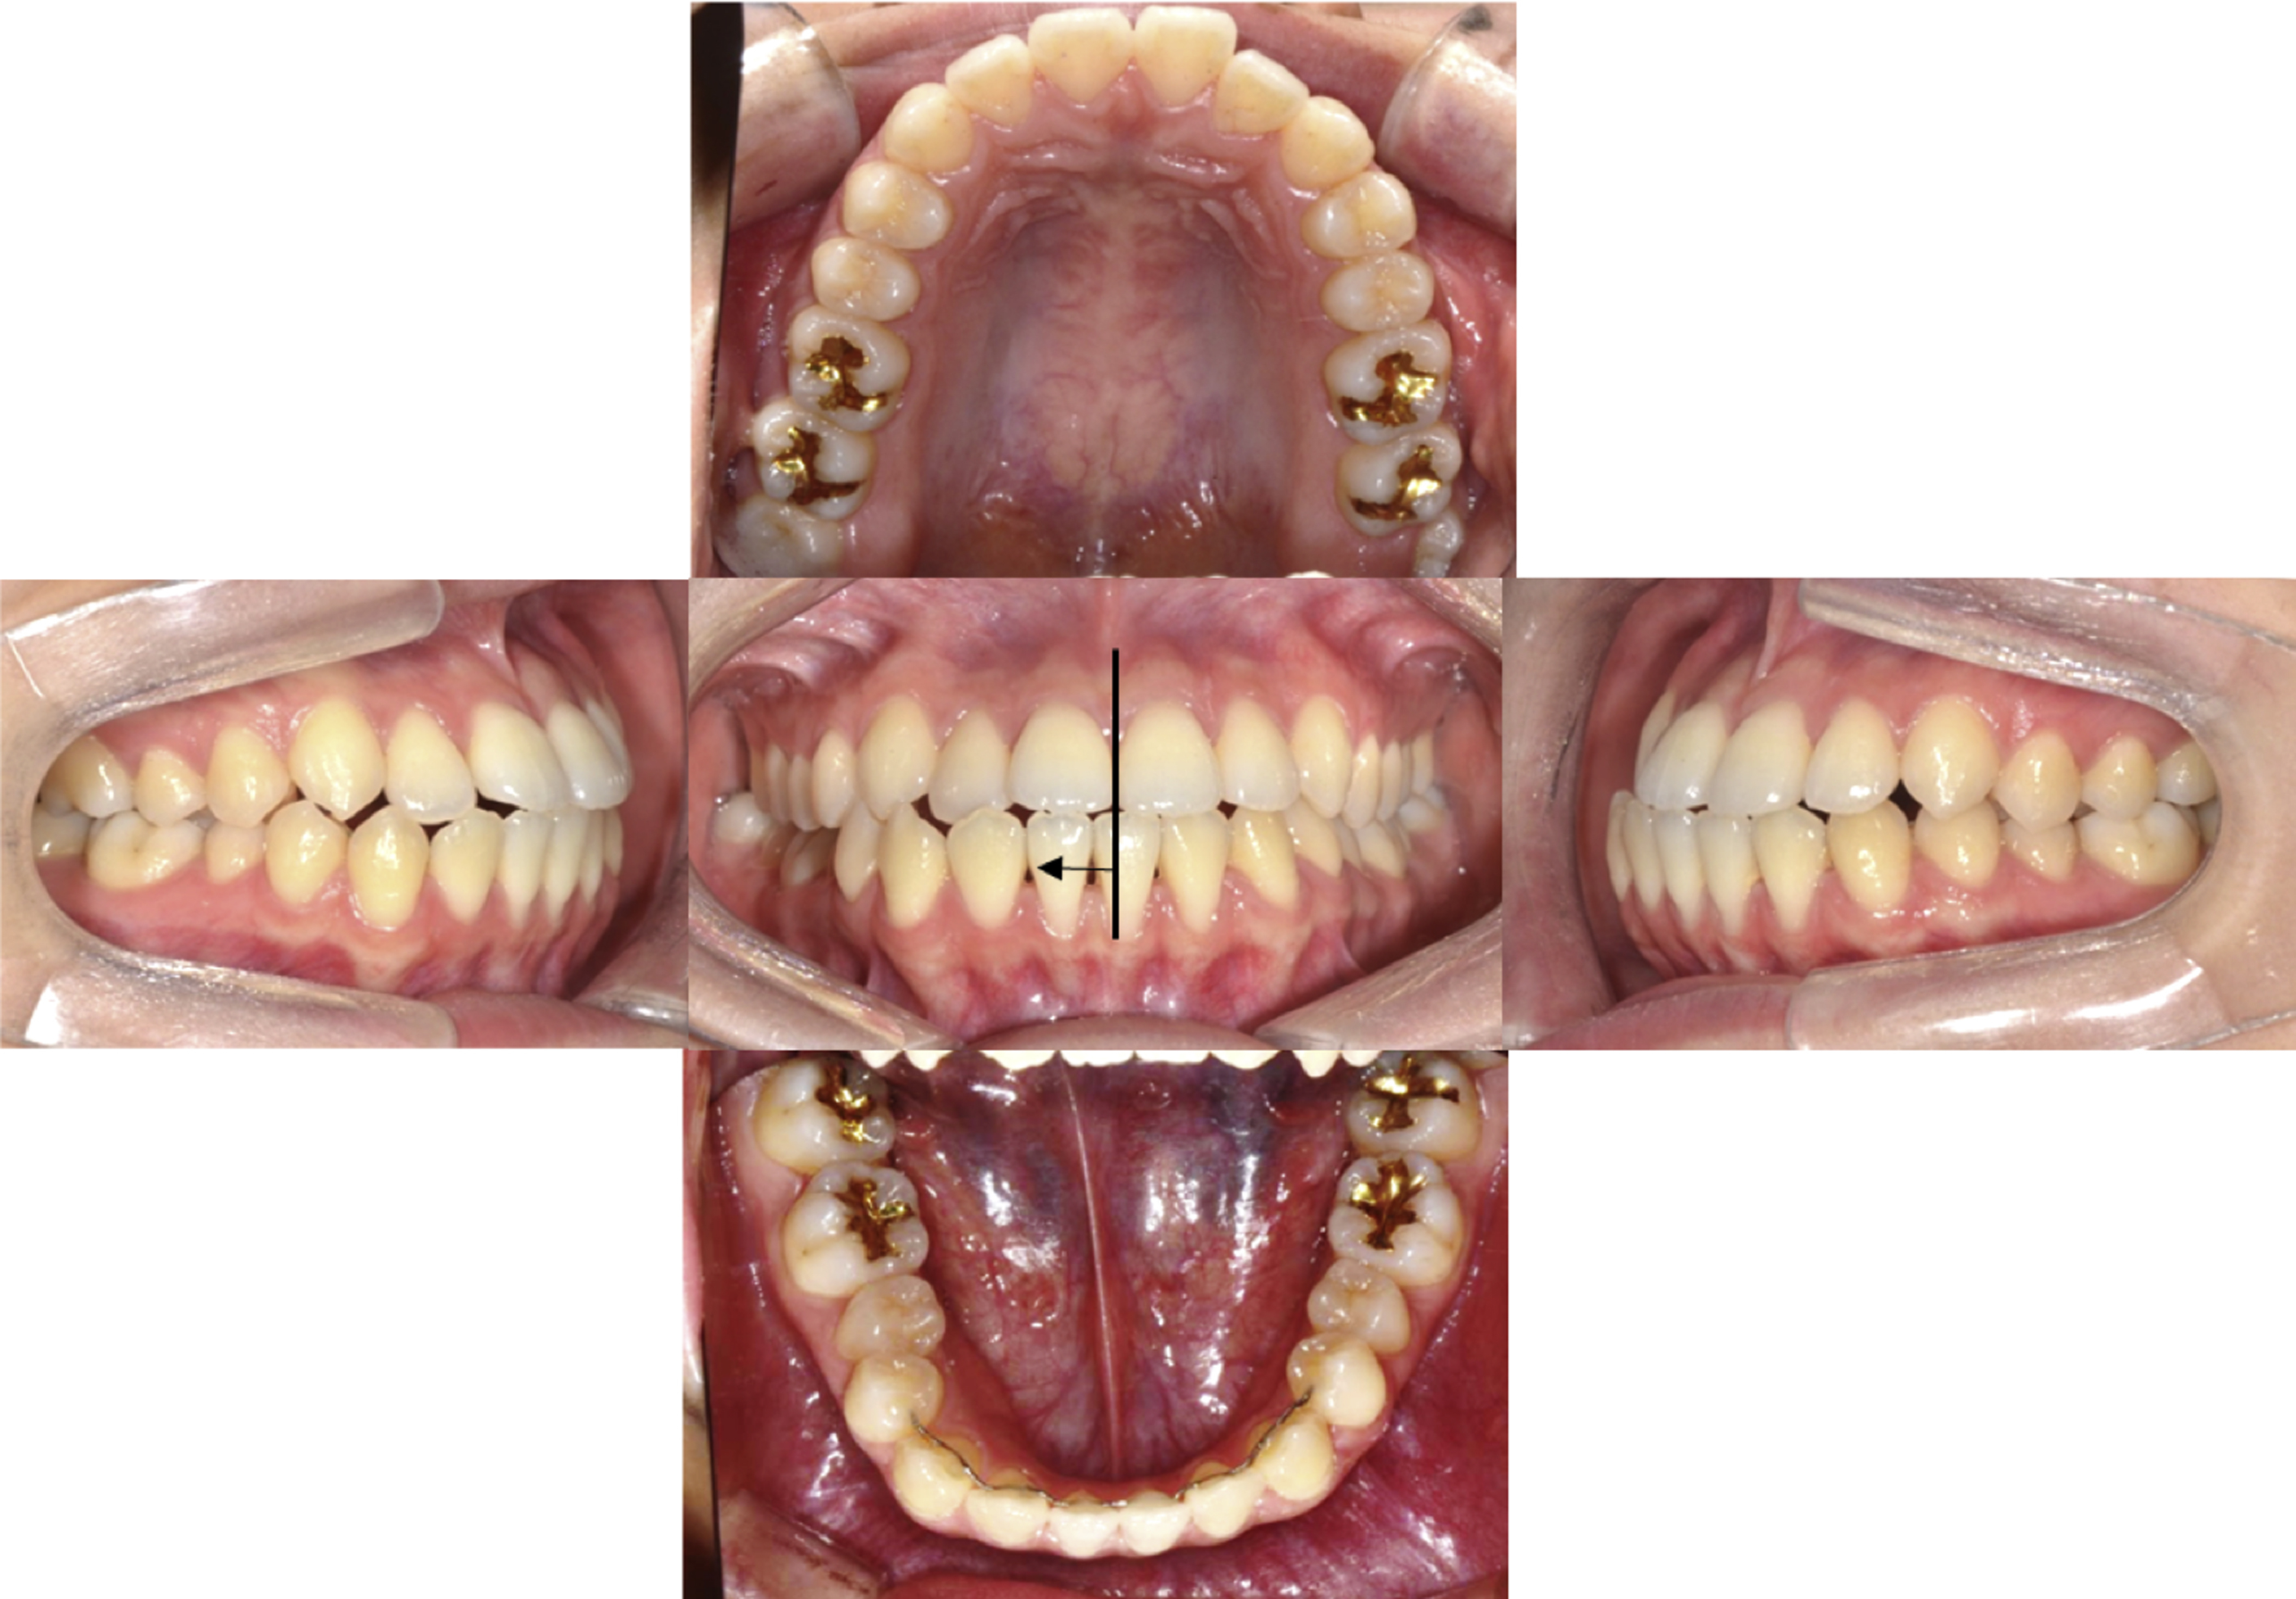

A 19-year-old female patient presented with the chief complaint of jaw protrusion and facial asymmetry. On a clinical examination, a midface deficiency with chin protrusion was observed ( Fig. 2 ). According to the intraoral photographs, an edge-to-edge bite with anterior open bite tendency was observed ( Fig. 3 ). Both the left and the right first molars showed a class III relationship, and the lower dental midline was deviated 2.5 mm to the right from the facial midline. In her smile photograph, a flat smile arc was observed.